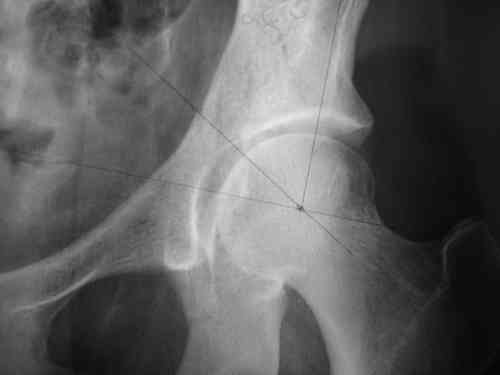

Маленькая иллюстрация (около 5 лет после травмы). Результат плохой - укорочение, хромота, периодически боли в спине, но больной отказывается от операции, видимо, не так все трагично.

А ведь показания для столь сложного оперативного лечения не выставляются по одной рентгенограмме не самого лучшего качества.

Как-то больной жил 6 лет, 3 года его ничего не смущало? (К плохому исходу тоже приспосабливаются.)

В чем причина декомпенсации и где ключи к победе?

По-моему они не столь очевидные.